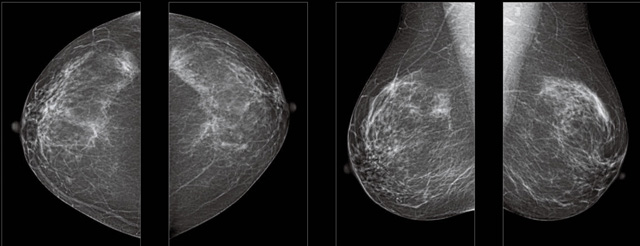

首先不同年龄阶段的乳腺筛查频次种类不一样。青春期女性第二性征明显发育开始,每个月进行自我乳腺检查。20-30岁的女性就不推荐进行乳腺检查,因为年轻女性的乳腺组织非常紧急。钼靶X光线等检查的射线不能辨别肿块跟腺体。身体就白吸收了辐射,影响了身体健康。每个月自检一次就是在洗澡时候,对着镜子看看乳房外观正常,皮肤溃烂、肿块、颜色改变、再摸一下有没小疙瘩。乳腺高危人群,特别是有乳腺CA遗传倾向的女性,乳腺导管跟小叶不典型增生,原位癌。30岁前有乳房放疗的女性。乳腺癌筛查可以把年龄提前到40岁前。40到70岁的女性可以在适合的机会筛查。

采用影像检查技术来发现疑似特定病检查跟人群的普查。一到两年进行一次X光线的乳腺检查。记过是C或者D型,可以加上B超协同。还可以一年一次核磁共振MRI检查。70岁以上的女性认为绝经的女性是比较安全的。实际上也有乳腺癌的风险。65岁以上风险也很大。也是需要进行机会性筛查。